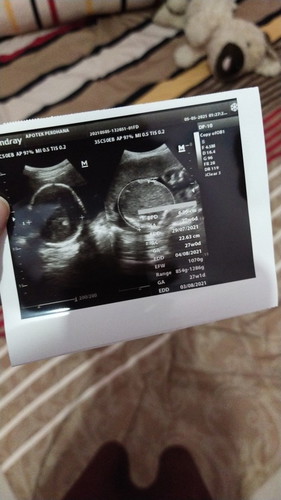

Mau crita BB janin ku pas USG buln lalu d usia 6 buln 4 Minggu , dokter bilang Janin udh 1 kg di tgl 23 buln 5 tepat nya 29 Minggu #seriusnanya #bantusharing #ingintahu #firstbaby janin udh 2 kg 2 ons , slama hamil aku cuma naik BB 1 kg aja , bagaimana dengan bunda"